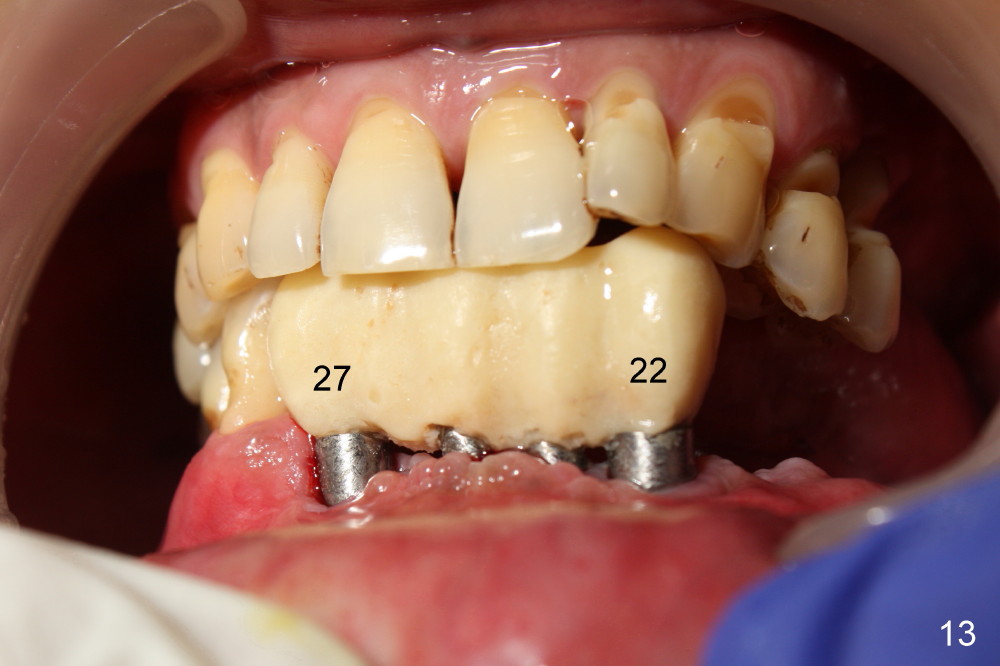

The rough surface of the implants at the sites of #22 and 27 is covered by the gingiva 2 months postop(Fig.13, as compared to Fig.10).